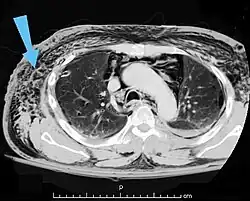

Verletzungen der Lunge können neben einer Lungenkontusion als Quetschverletzung Lungenrisse sein. Letztere führen zu einem Pneumothorax, wie er bei 10 bis 50 Prozent der Patienten mit Thoraxtrauma auftritt,[6] und gegebenenfalls zu einem Spannungspneumothorax. Blutungen in den Thorax hinein führen zu einem Hämatothorax. Bei einem Hämatopneumothorax treten sowohl ein Pneumo- als auch ein Hämatothorax in Kombination auf. Symptome sind zunächst Luftnot und je nach Ausmaß der Blutung auch Kreislaufinstabilität. Bei einem Pneumothorax kann sich insbesondere bei Ausbildung eines Spannungspneumothorax ein Hautemphysem bilden, das eine große Ausdehnung erreichen kann. Therapie ist eine Entlastung der Pleurahöhle mittels Thoraxdrainage auf der betroffenen Seite. Üblicherweise kommen kleinere intrathorakale Blutungen von alleine zum Stehen, so dass außer einer Drainage keine weiteren Maßnahmen notwendig werden. Eine Thorakotomie zur operativen Blutstillung kann bei einem initialen Blutverlust von mehr als 1.500 ml nach der Thoraxdrainage oder bei einem fortwährenden Blutverlust von mehr als 250 ml pro Stunde über mehr als vier Stunden erfolgen.[2][5]

Die Kombinationsverletzung von Thorax und Abdomen ist die vierthäufigste Kombination bei mehrfachverletzten Patienten.[2] Insbesondere Zwerchfell, Leber und Milz sind auch bei isolierten Thoraxtraumen oft mitbetroffen. So können beim stumpfen Thoraxtrauma gebrochene Rippen in Leber oder Milz spießen und starke Blutungen verursachen. Durch ein plötzliches Kompressionsereignis kann das Zwerchfell ein- oder beidseits rupturieren und es kann zur Verlagerung von Bauchorganen in den Brustkorb kommen. Hierbei kommt es zu einer mechanischen Kompression der Lungen mit Luftnot und abgeschwächtem Atemgeräusch auf der betroffenen Seite. Bei einer rechtsseitigen Zwerchfellruptur liegt mit sehr großer Wahrscheinlichkeit auch eine schwere Verletzung der Leber vor.[2] Bei penetrierenden Thoraxtraumen können die in den Körper eindringenden Fremdkörper wie Projektile oder Messer sich bis in den Bauchraum bewegen und dortige Organe mitverletzen.[2] Symptome von intraabdominellen Organverletzungen sind Schock und Anzeichen eines akuten Abdomens.[2]